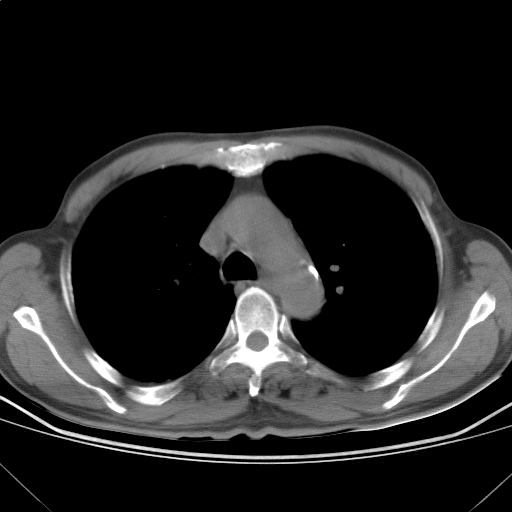

以下是引用随光逐影在2009-5-1 13:53:00的发言:[br]考虑为:1)两肺血行播散型肺结核;2)右肺下叶炎症感染。3)右侧胸膜增厚。